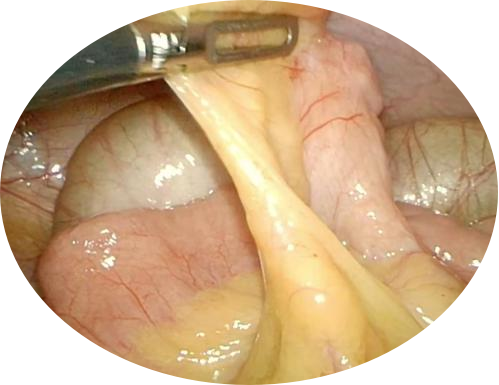

2.隐睾

隐睾恶变为睾丸肿瘤的几率比正常睾丸高10多倍,位置越高,手术时间越晚,恶变几率越大。故腹腔型隐睾更应尽早进行手术治疗。但鉴于彩超、CT、磁共振对腹腔内软组织的分辨率有限,特别是发育不良的睾丸,腹腔镜手术成为腹腔内隐睾治疗的金标准。腹腔镜的最大优点是不破坏腹股沟区解剖结构,准确定位睾丸位置,避免了盲目探查,在腹腔内充分松解精索血管,输精管,使其无张力下降至阴囊底部固定,损伤小、恢复快、住院时间短、伤口0.3~0.4cm,无疤痕。还能同时探查了解对侧内环口有无闭合、腹腔内肠管有无畸形并同时处理等优点。